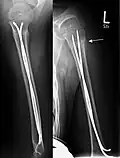

Komplette Unterarmschaft-fraktur beim Kind mit deutlicher Knickbildung -

Versorgung derselben Fraktur mit je einem Prevot-Nagel (ESIN) in Radius und Ulna